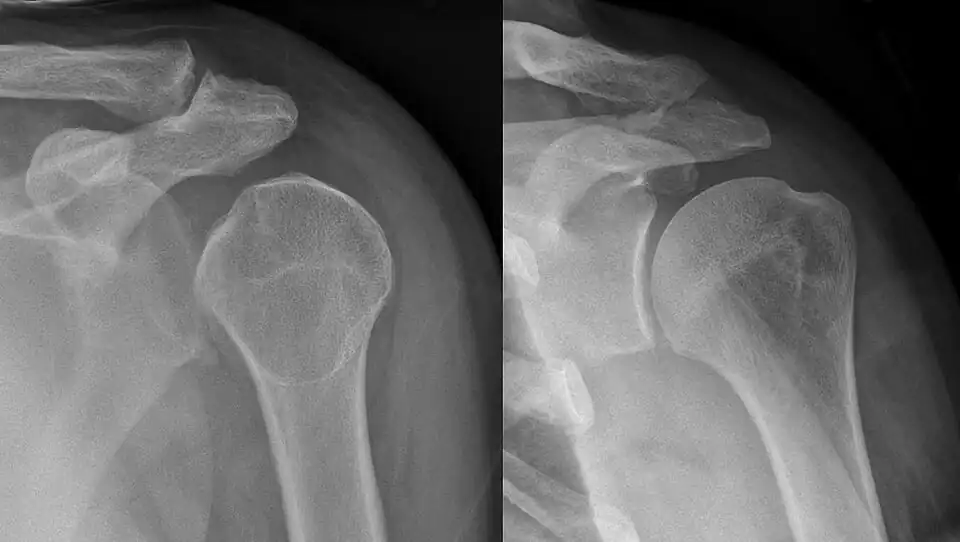

A Hill–Sachs lesion is an impaction of the head of the humerus left by the glenoid rim during dislocation.[6] Hill-Sachs deformities occur in 35–40% of anterior dislocations. They can be seen on a front-facing X-ray when the arm is in internal rotation.[11] Bankart lesions are disruptions of the glenoid labrum with or without an avulsion of bone fragment.[12]

An anterior dislocation of the shoulder

Anterior dislocation of the right shoulder. AP X ray -

Anterior dislocation of the right shoulder. Y view X ray.